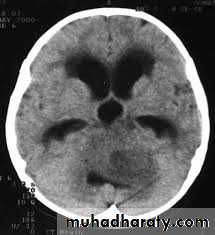

Posterior fosse tumor

Medullo blastoma

Age incidence between 5-15 Y represent about 35-40 %of PFT

Arise from the midline mainly within or from the roof of the 4 TH ventricle fill the fourth ventricle & seeding via the csf so can seen in the distal part of the spinal canal .

CT finding as well circumscribed lesion heterogeneous in density ,have solid & cystic part , with also scattered calcification little surrounded edema , the solid part is enhance

90 % present with obstructive hydrocephalous at the level of the 4Th V. with dilatation of the lateral V. ( body , frontal , temporal & third ventricle )